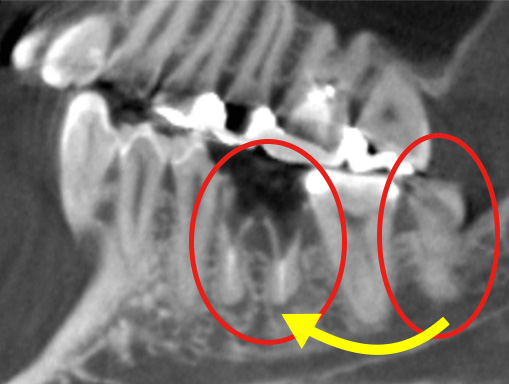

CT像では歯の生え方や神経の走行、上顎洞との位置関係などを3次元で確認することができるため、より正確な診断が可能です。主治医が総合的に判断しCT撮影を提案された場合はより安全な抜歯のために受けることをお勧めいたします。また患者様のご希望でも撮影は行いますのでお申しつけください。

親知らずの歯根の先端と下顎神経が近接している場合は2回に分けて抜歯を行うことがあります。まず、親知らずを2分割して頭の部分を抜きます。その後しばらく期間をおいて、のこる歯根の部分が頭を抜いたスペースに移動したのを確認して抜きます。

このように2回に分ける事で安全な抜歯が可能です。

まず歯冠を切除し、疼痛がでないよう、冠部歯髄を除去してネオダイン(歯髄の鎮痛鎮静、象牙質の消毒、覆髄)を填入します。その後、粘膜骨膜弁にて完全閉鎖を行います。以下に処置の流れを示します。

処置の評価

歯冠切除量と歯根の移動量の結果です。術前の智歯(親知らず)の幅径に対して計測した智歯の長径の割合は1.21ポイント、術後は1.10ポイントで有意に差を認めました。数ヵ月待機することにより歯根は有意に近心側に移動していることを認めました。

CT -